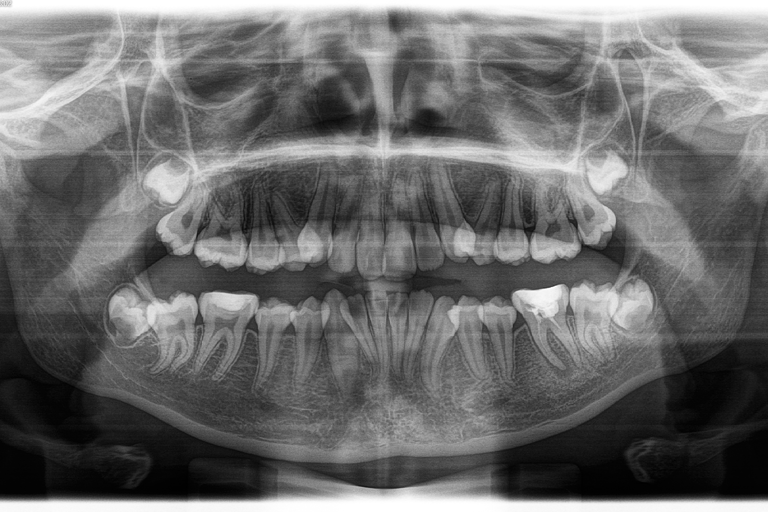

- Radiographies panoramiques : Ce type de radiographie offre une vue complète de votre bouche, y compris vos dents, votre mâchoire supérieure et inférieure, vos sinus et vos articulations temporo-mandibulaires. Elles sont généralement utilisées pour planifier des traitements orthodontiques ou des interventions chirurgicales, ou pour évaluer l'état de la mâchoire et des dents de sagesse.